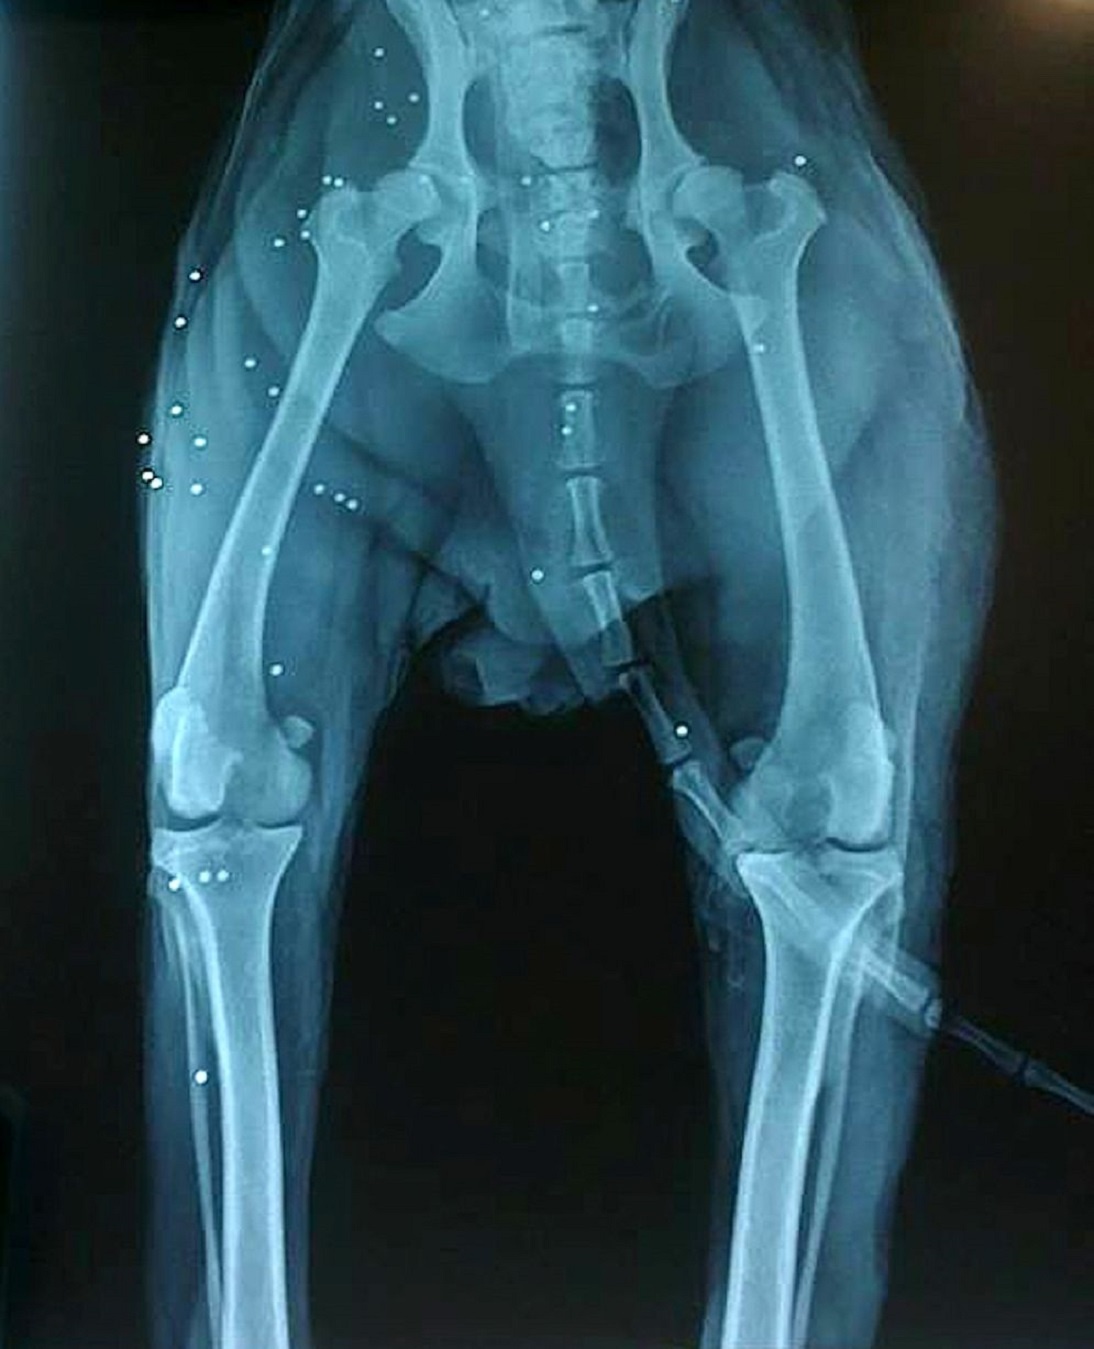

| Con chó săn lông xù hai tuổi trúng 38 viên đạn tẩm độc và đang hấp hối. Bác sĩ buộc phải sử dụng thuốc liều mạnh. Con chó tỉnh lại khi mọi người gần hết hy vọng. Sau đó, sức khỏe của nó phục hồi dần. |